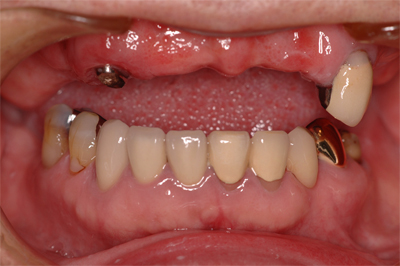

インプラント施術例

歯を削りたくない、入れ歯をどうしても入れたくないという時、インプラント治療を行っています。

施術前

施術後